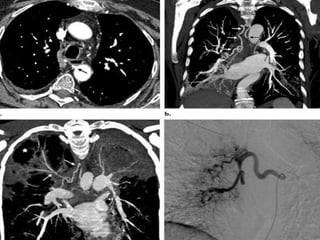

Bronchial artery embolization

• Bronchial artery embolization is highly effective in the

treatment of acute hemoptysis. Short-term non

recurrence rates (with follow-up up to 1 month) range

from 77% to 99% .

• success rates of 100% can be achieved using repeat

embolization and control of underlying disease either

pharmacologically or surgically .

• The most effective nonsurgical treatment for massive

hemoptysis is bronchial artery embolization (BAE) .

(Chun and Belli , 2009)

• Bronchial arteryembolization is highly effective in the treatment of acute hemoptysis. Short-term non recurrence rates (with follow-up up to 1 month) range from 77% to 99% . • success rates of 100% can be achieved using repeat embolization and control of underlying disease either pharmacologically or surgically . • The most effective nonsurgical treatment for massive hemoptysis is bronchial artery embolization (BAE) . (Chun and Belli , 2009)